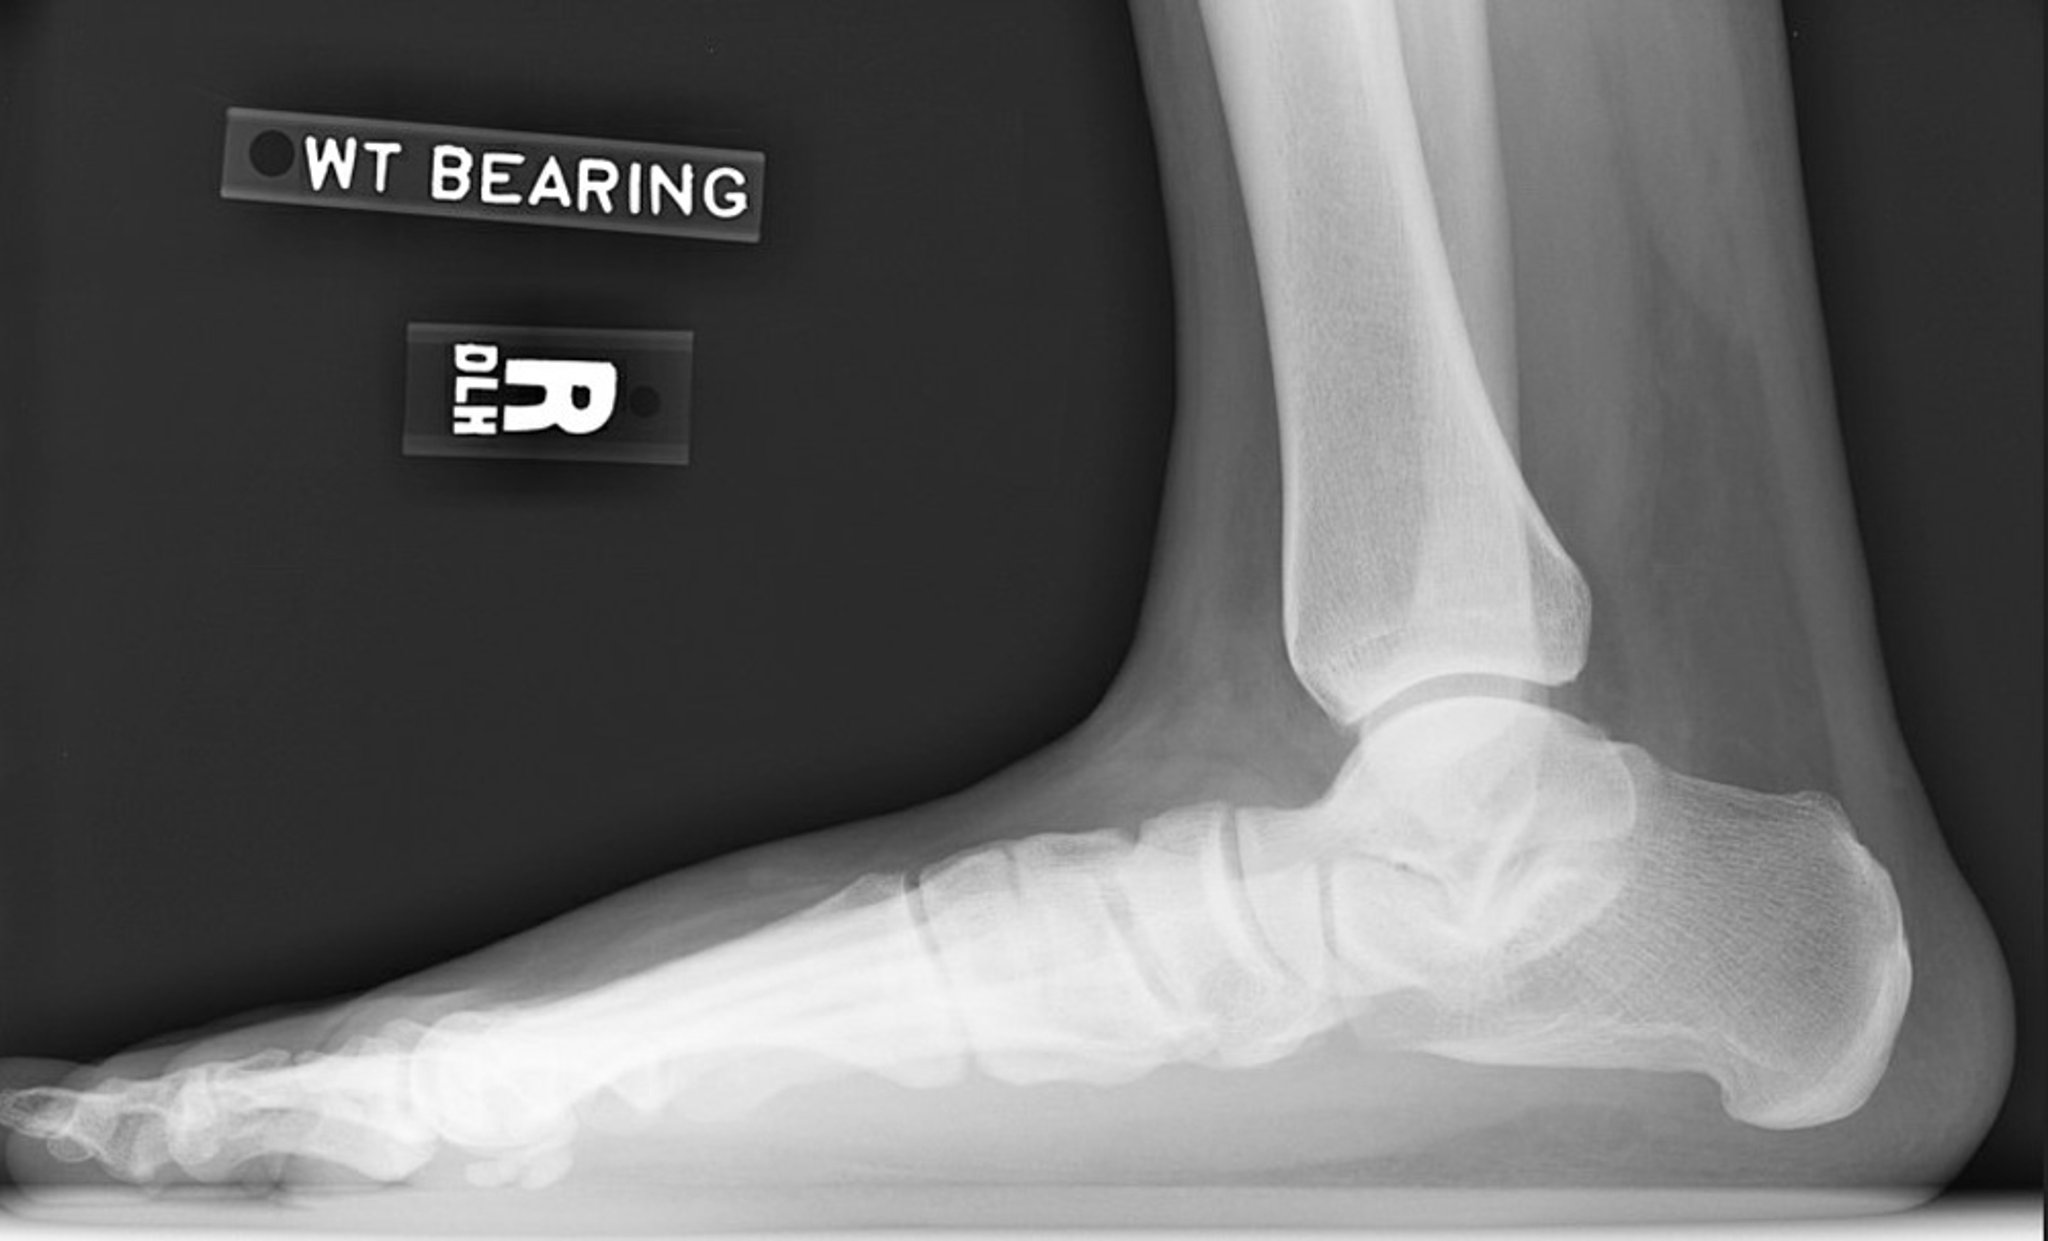

Рентгенограма при плоскостопості

Lateral radiograph of right foot showing loss of arch height. Note the decreased calcaneal inclination angle and decreased talar declination angle. The subtalar joint is narrowed but the ankle joint is relatively preserved.

Image courtesy of James C. Connors, DPM.